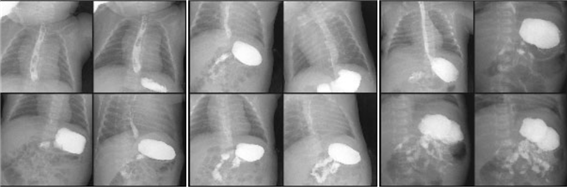

소아 조영술 검사

목적 : 검사방법, 소요시간, 준비물, 검사 후 주의사항은 성인 검사에 준하나 전처치의 차이가 있습니다.

선천성기형, 위 식도 역류, 비루성 유문 협착 등을 진단합니다.

1)Esophagography

2) UGI